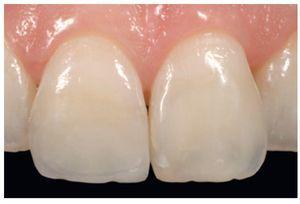

Figura 17 Paciente de 8 años de edad, con fractura traumática de los dientes 11 y 21.

Figura 18a y b Para conseguir una restauración estéticamente atractiva es importante controlar de forma concienzuda las capas de dentina y esmalte.

Figura 19 El caso, en una revisión después de un año.